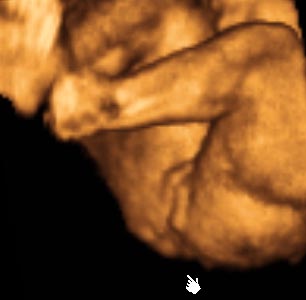

香港结构超声波照片

结构性超声波, 四维 香港, 四维结构性超声波 结构性超声波, 四维 结构性超声波, 四维 香港, 四维结构性超声波 结构性超声波, 四维 香港, 四维结构性超声波 结构性超声波, 四维 结构性超声波, 四维 结构性超声波, 四维 香港, 四维结构性超声波 结构性超声波, 四维 香港, 四维结构性超声波 结构性超声波, 四维 结构性超声波, 四维